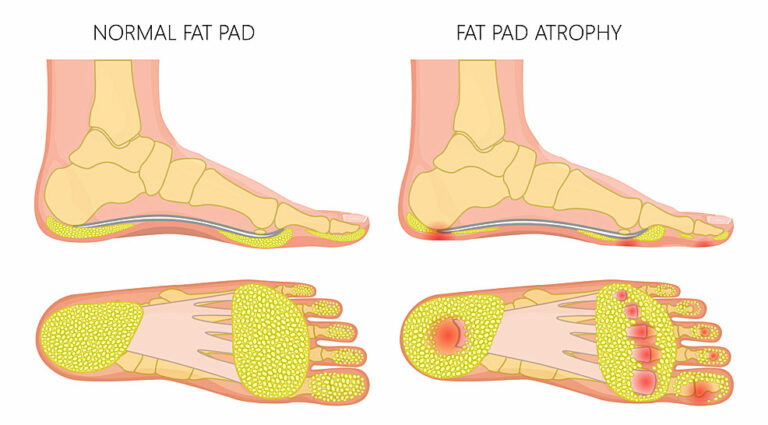

Fat pad atrophy

Fat pads serve as cushioning and shock absorbers in our feet, protecting the bones, joints, and soft tissues from impact during movement. Preserving these natural shock absorbers is vital for foot health.

Fat pads are located under the ball of the foot and the heel. They consist of thick connective tissue that helps distribute pressure evenly across the foot, providing extra heel support and reducing heel pain.

However, if the fat pads diminish due to old age or injury, it can lead to foot pad atrophy and heel pad syndrome, can result in degenerative foot conditions like plantar fasciitis, causing severe foot pain and discomfort.

It can significantly impact a person’s mobility and quality of life. If left untreated, pad atrophy can result in worsening foot pain, altered gait, and increased risk of falls and injuries.